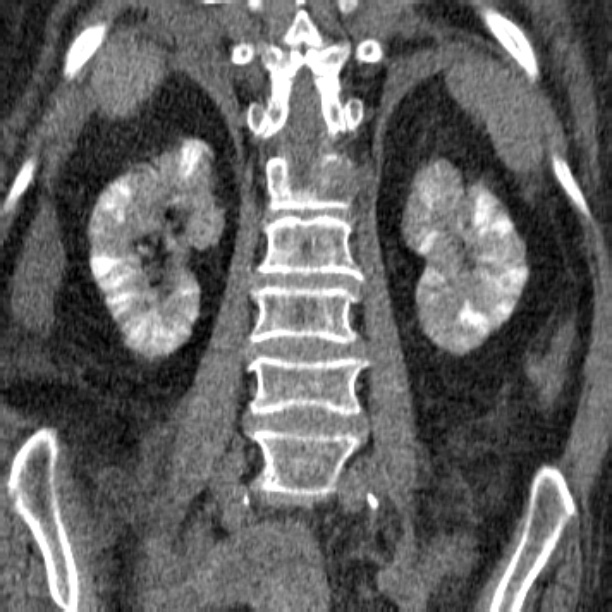

SPOTTED NEPHROGRAM

Figure 5A

A late arterial phase from an aorto- gram shows bilateral spotted neph- rognams in a patient with polyartenitis nodosa.

Figure 5B

This is a late phase from a selective renal arteniogram in the same patient; it demonstrates occlusion of multiple peripheral vessels with cortical irregu- lanity.

https://pubs.rsna.org/doi/pdf/10.1148/radiographics.6.6.3685518